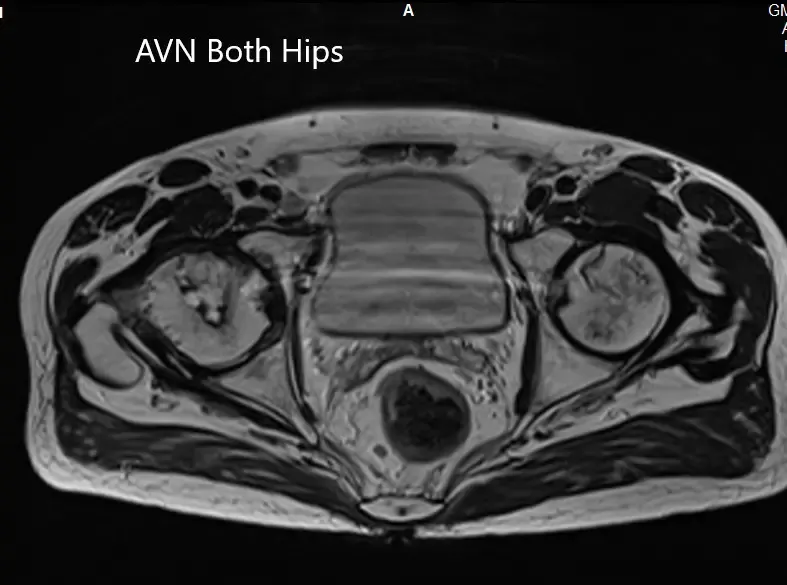

MRI showing bilateral femoral head AVN in T2WI

Axial sections of T1WI and T2WI showing bilateral AVN of the femoral heads